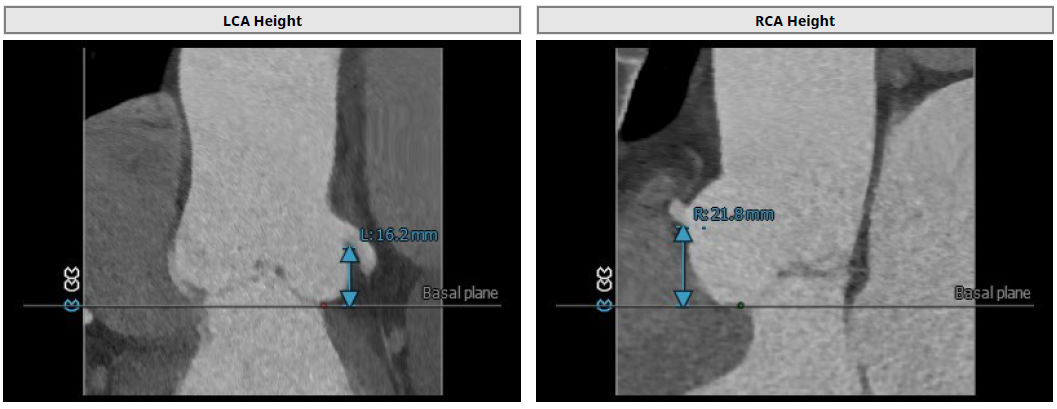

3.患者双侧冠脉开口高度可LCA:16.2mm,RCA:21.8mm;

左冠高度:16.2mm;右冠高度:21.8mm

窦管交界:39.9mm;升主动脉:44mm